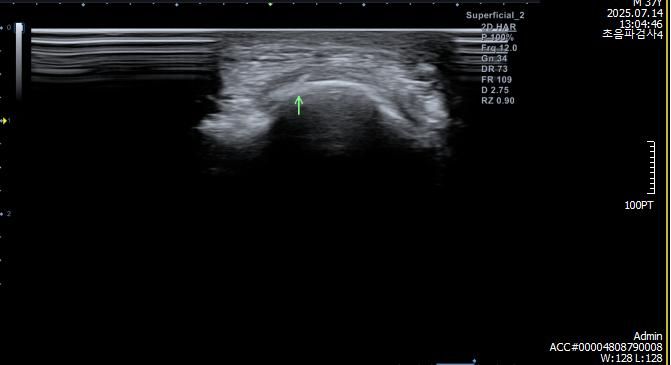

검사 결과 (7월 중순)

- MRI: 좌측 삼두건 경미한 염증, ulnar nerve supracondylar level 경미한 신호 증가

- 초음파/근전도: 척골신경 아탈구 확인

아래는 관련 사진 첨부합니다.

• 1번 째 사진